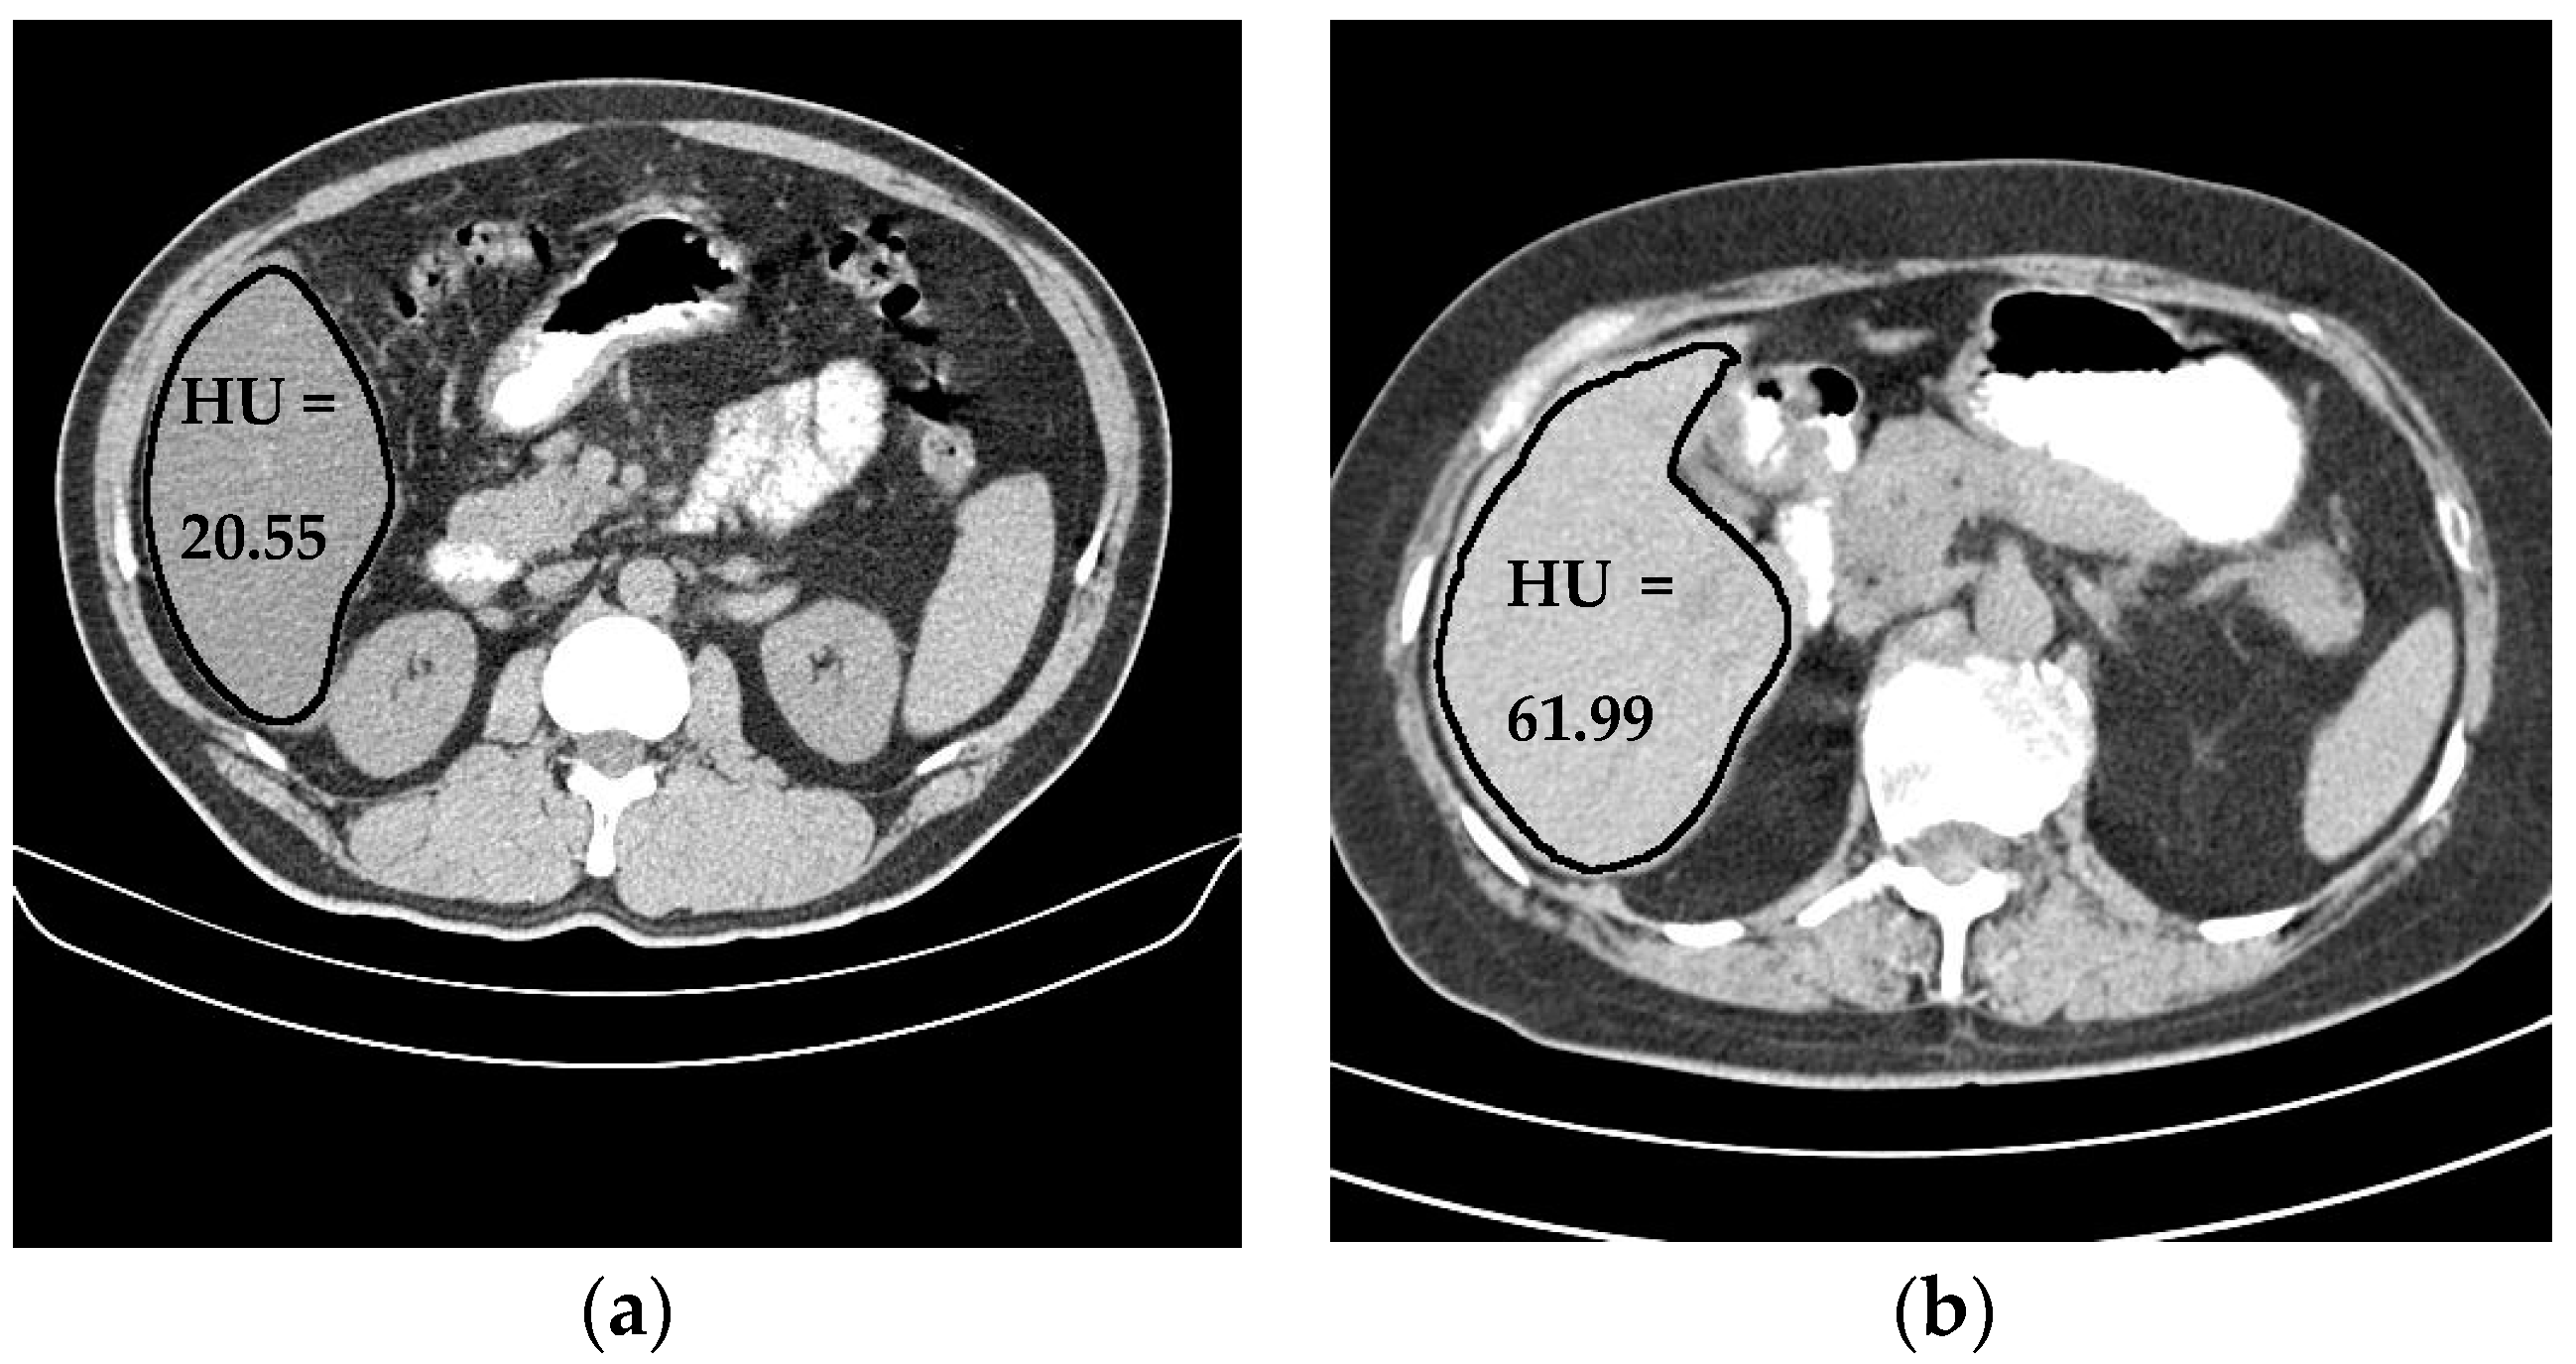

Liver density is inversely related to liver fat, according to Ricci et al. [7]. The mean of the liver HU values for the used data set was employed as an indicator for the level of diffused fat in the liver. Figure 13 illustrates two examples of two CT images (two different subjects) where the liver is bounded by black contours using the proposed liver segmentation method. The liver in each example shows different tissue densities.

Figure 13.

Variation of liver HU values. (a) Low HU value, (b) high HU value.